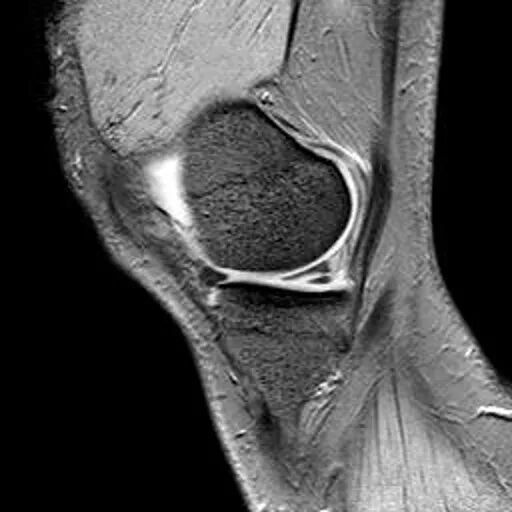

半月板纵行撕裂

1、纵行撕裂2、撕裂方向和半月板长轴方向平行3、垂直或斜行的III级高信号

(半月板纵行撕裂)